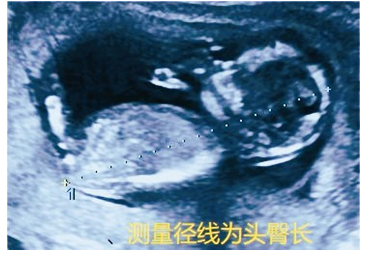

孕11-13周此时的TA初具人形,长度(头臀长)在5~8厘米,在超声下很容易被看见,而且一眼万年(图5-1)。超声下的TA展示出大体的解剖结构如颅脑、心脏、肢体,腹腔脏器等等,因此我们正式称之为胎儿。孕11-13周的胎儿非常适合进行NT(胎儿颈项透明层)的检查(图5-2),以评估胎儿患唐氏综合征的风险。

图5-1 超声显示:宫内妊娠